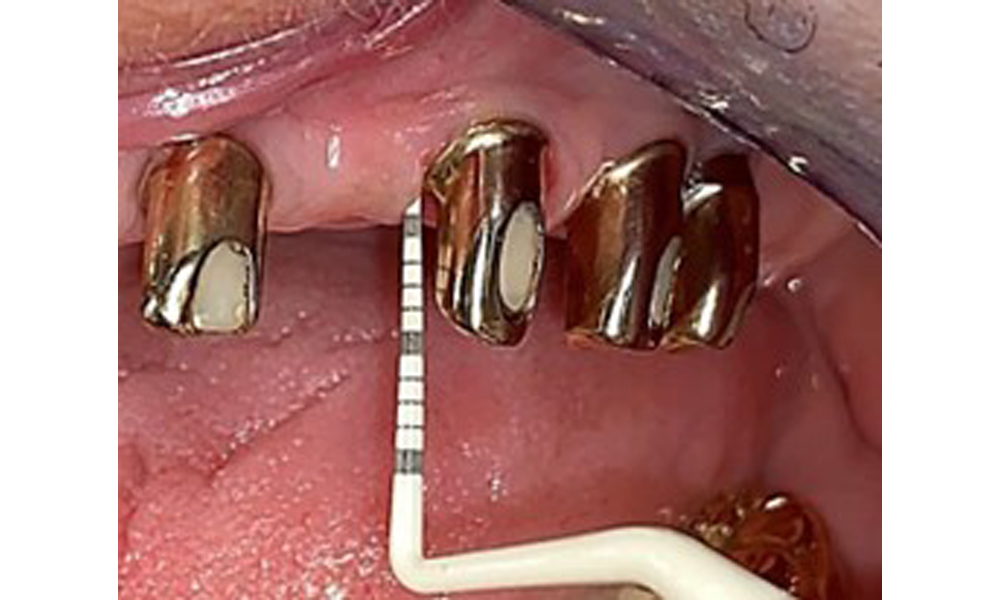

The patient was fitted with a combined removable maxillary telescopic prosthesis more than 25 years ago (Fig. 1, Fig. 2, Fig. 3) and is very happy with her dentures. The patient has an adequate fixed denture for the mandible (Fig. 4).

The dental findings are as follows: Combined removable implant and tooth-supported telescopic prostheses on implants 15, 13, 21, 23, 24, 25 and tooth 11 (Fig. 1, Fig. 2, Fig. 3). The patient was fitted with a fixed mandibular denture. Adequate bridges were present over 37 to 34 and 45 to 47 (Fig. 4), the crown margins were intact and there were no active caries. A composite filling with a marginal gap was present on tooth 43. There was mandibular gingival recession, exposing 1 to 3 mm of root surface. This also applies to 11.

The intraoral mucosa must be examined for possible fungal infections and pressure spots. The dentures must be visually inspected for cleanliness. The present case presented with interdental discolouration, attributed to tea consumption (Fig. 7). The dentures should be professionally cleaned in the dental practice using disinfection and cleaning baths.